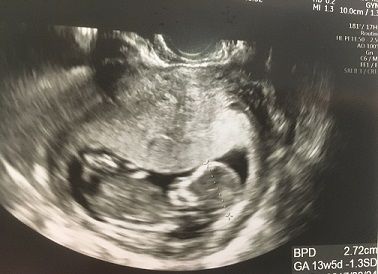

妊娠4ヶ月 妊娠12週 13週 14週 15週 妊娠初期 の超音波写真 妊娠 出産 育児に関する総合情報サイト ベビカム

妊娠14週目エコー写真 胎児の大きさ お腹の張りは大丈夫 妊娠初期 All About

妊娠14週目 14w0d 6d のエコー写真とエピソード 妊娠4ヶ月 Cozre コズレ 子育てマガジン